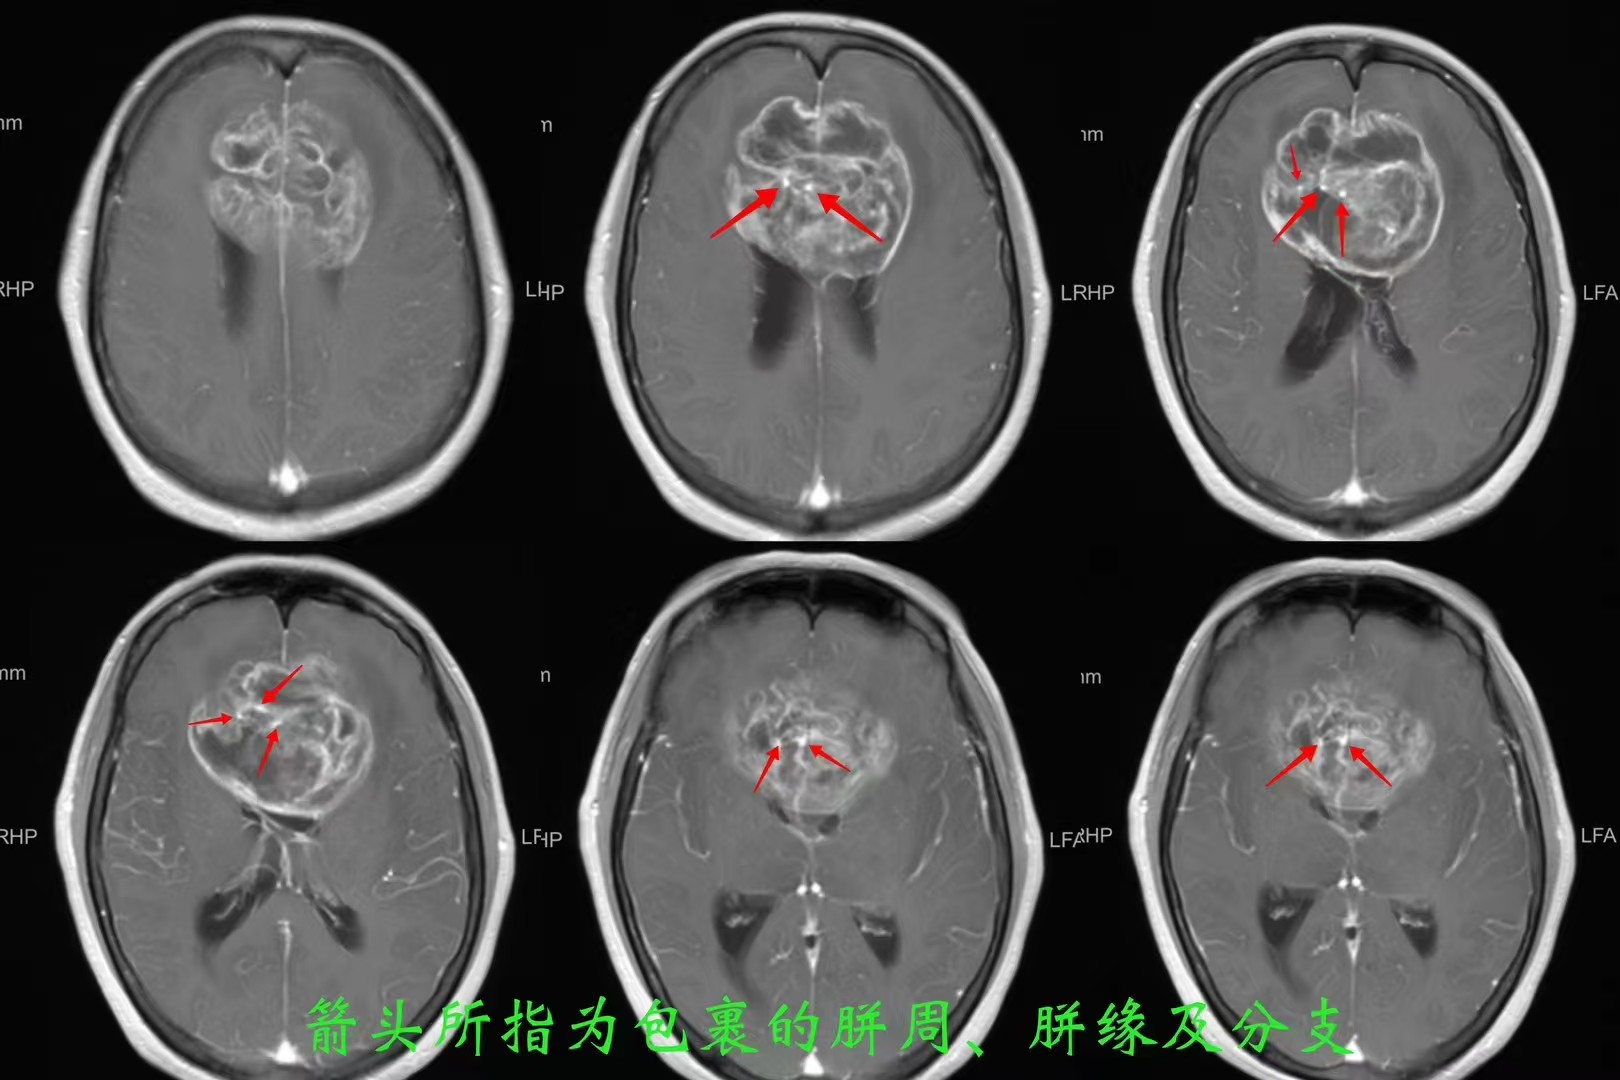

患者,女性,58岁,因“反应迟钝、记忆力下降1月,加重伴头痛、恶心、呕吐1周”入院。